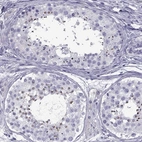

Immunohistochemical staining of human testis shows strong positivity in spermatids.